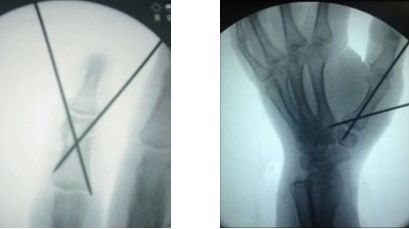

此外,虽然微型钢板已经普及,但是克氏针在掌指骨骨折的治疗中仍然占据着统治地位。

7、克氏针临时固定

克氏针不仅可以对骨块进行临时固定,达到良好的复位,为置入内植入物创造环境;也可以对内固定物进行临时固定,方便下一步操作。